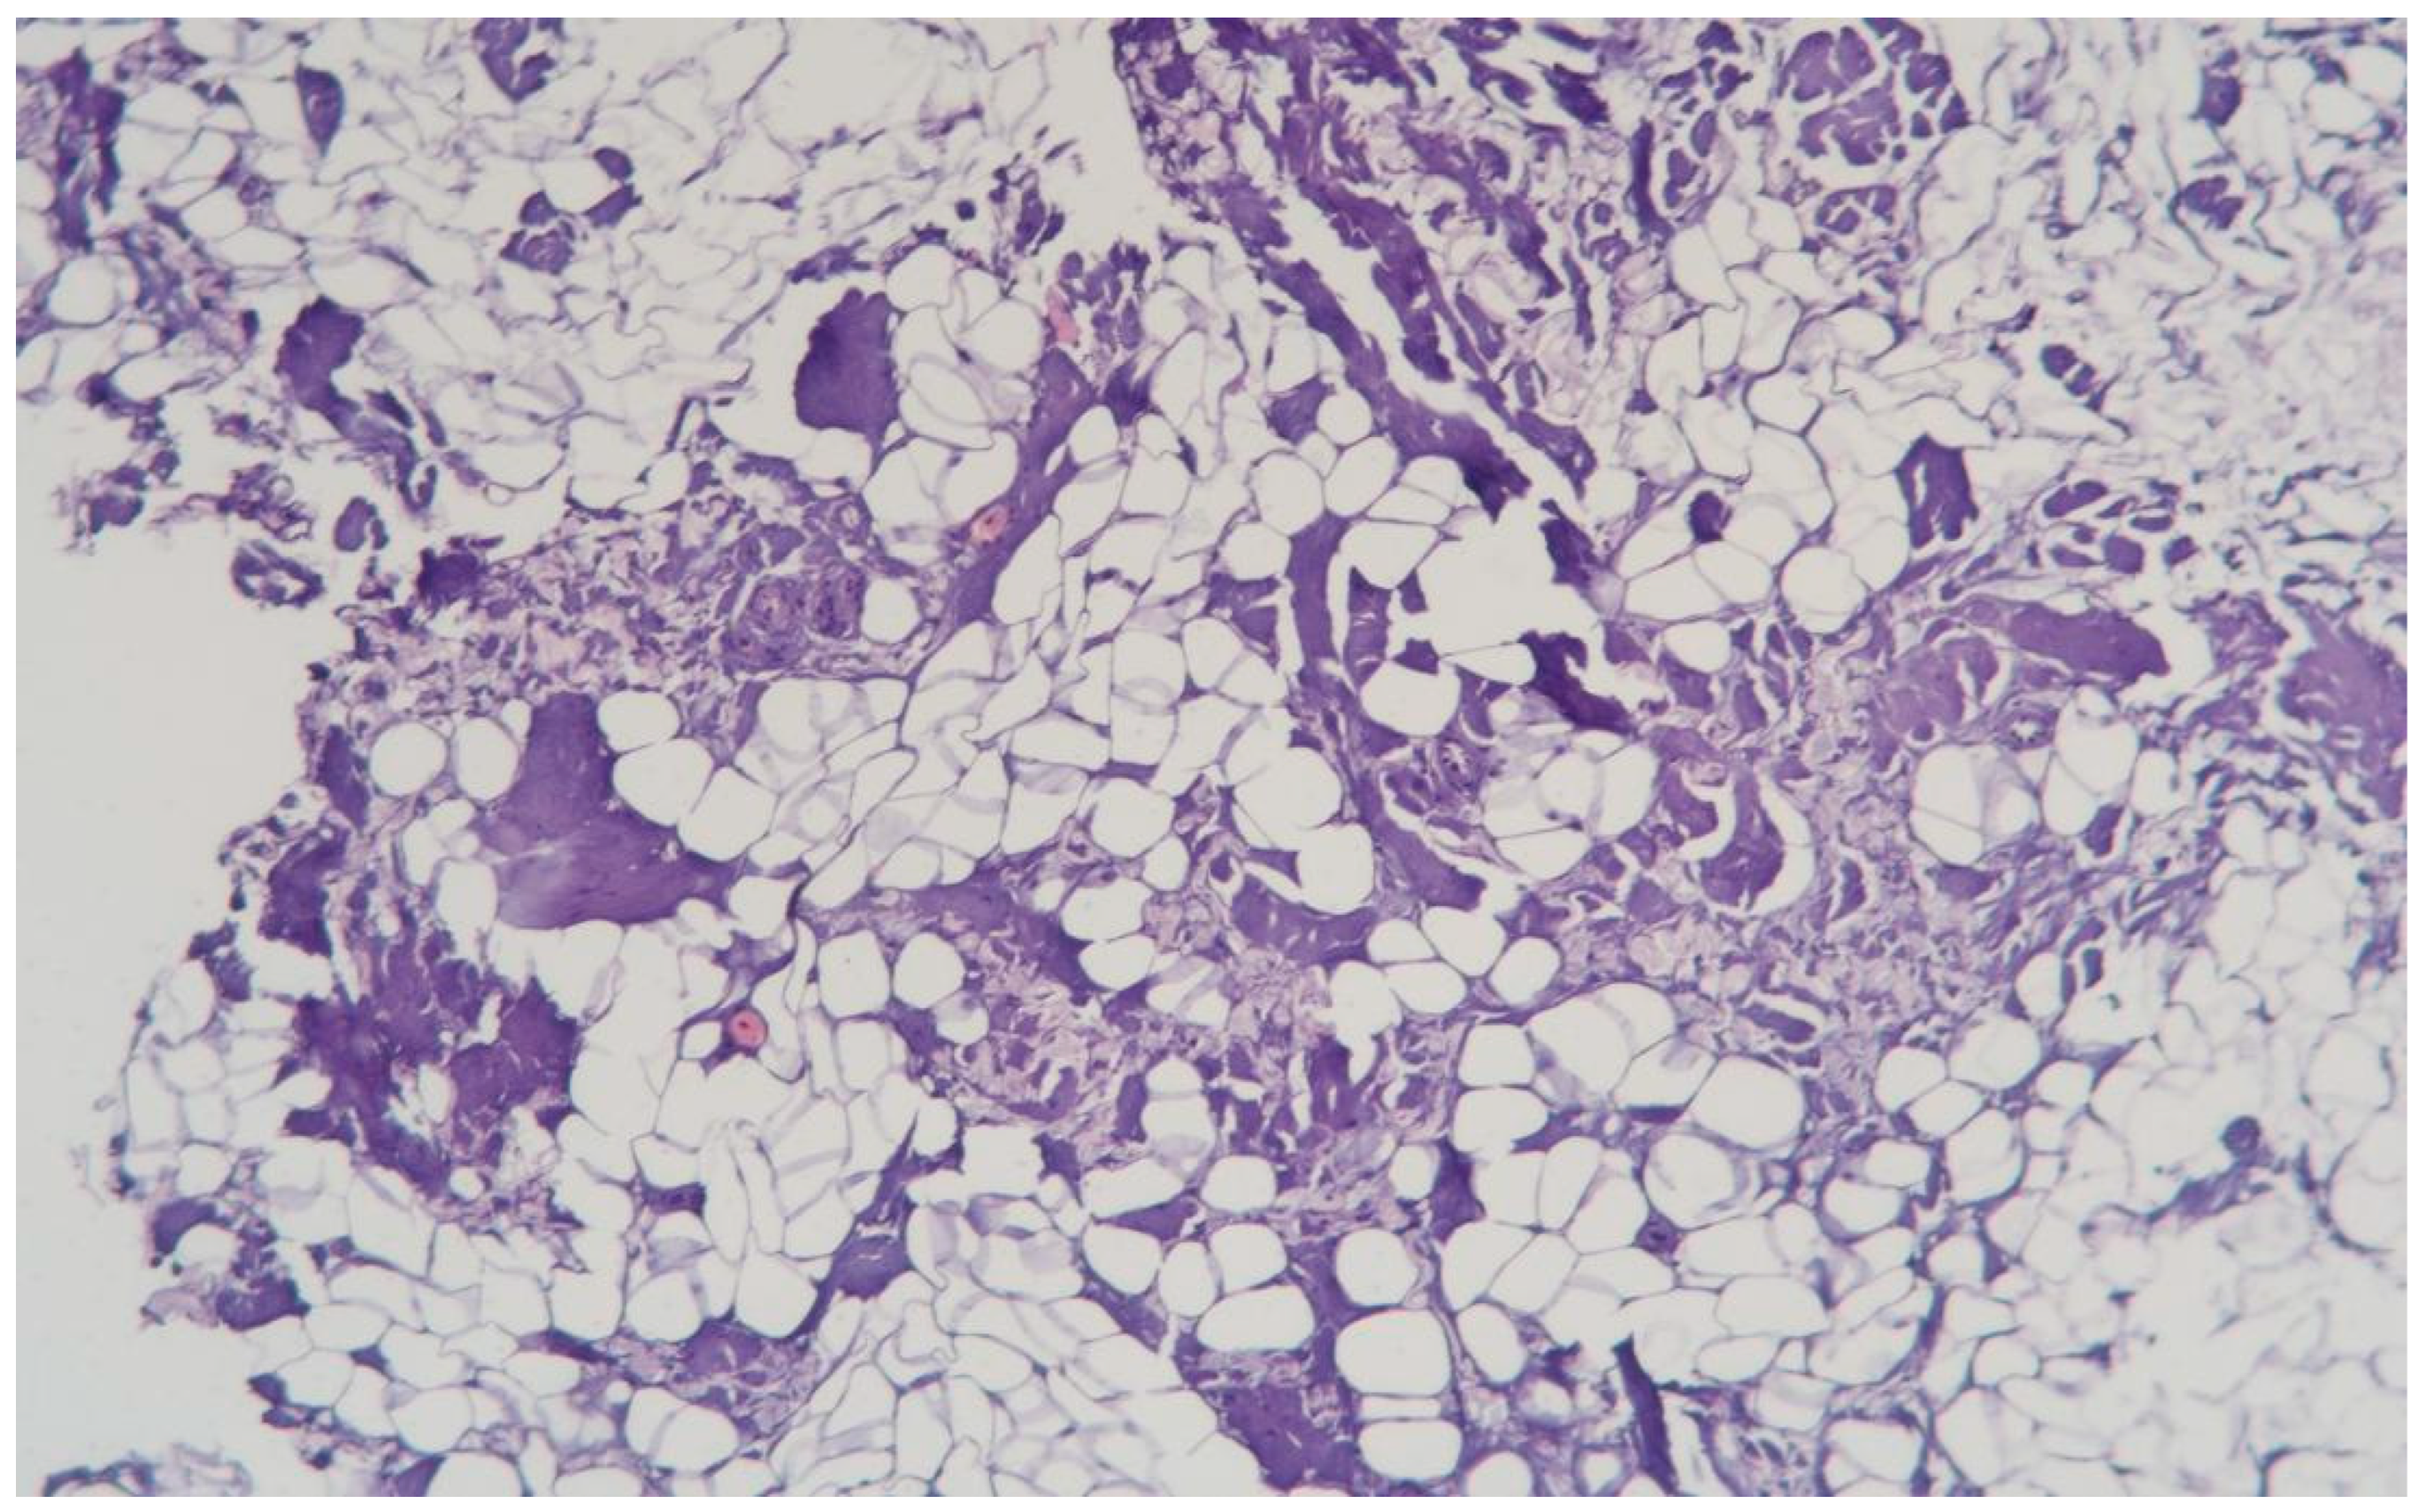

3.1.8. Clinical Case 8: Adipose Tissue Dissection Area, 15 W (See Figure 9)

Description: The coagulative necrosis of the adipose tissue was primarily along the septa. The vessels in the subcutaneous adipose tissue were congested; small-caliber vessels were coagulated, while larger vessels showed necrosis of the perivascular space, polarization, and sloughing of endothelial cells. Inflammatory changes were absent.

Figure 9. Changes in subcutaneous adipose tissue following exposure to the thulium laser at 15 W 75 Hz. H&E staining, 10× objective magnification.